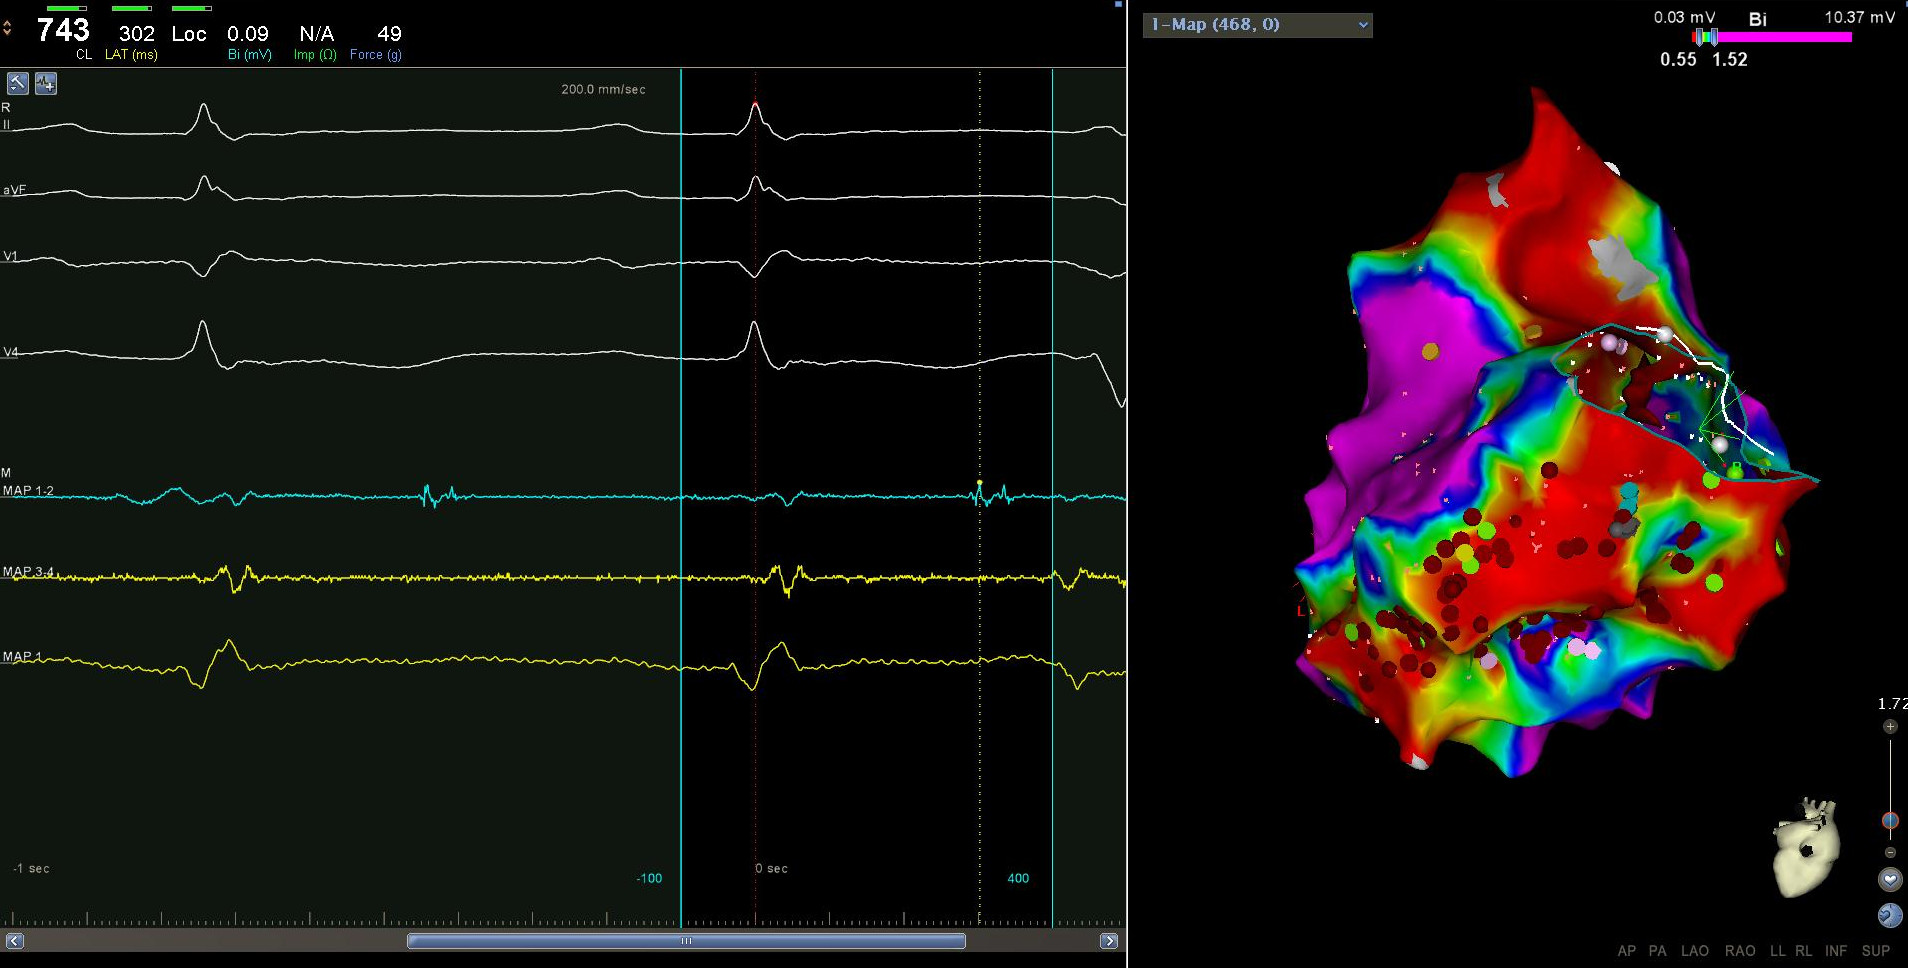

Sinus rhythm or pacing ?

• Bipolar voltage comparable in sinus rhythm / ventricular pacing (1)

• RV pacing better than sinus to identify late potentials (2)

Sinus rhythm or pacing

rv_pacing_lp.gif

Arenal et al. Ablation of electrograms with an isolated, delayed component as treatment of unmappable monomorphic ventricular tachycardias in patients with structural heart disease. JACC 2003;41:81.

Prefer pacing unless

• Ventricular pacing not tolerated

• RV being mapped

Pacing for RV mapping

bhavani_lp_sinus_rv_pace.jpg

Unknown

• multiple pacing vectors at each point

• LV pacing for RV substrate ?

• Extrastimuli ?

Choosing a window

anatharaj_vlp.jpg

Setting gain

bip_gain.gif

Identifying abnormal electrograms

• Setting right gain

• Operator supervised annotation

• 'Beat averaging'